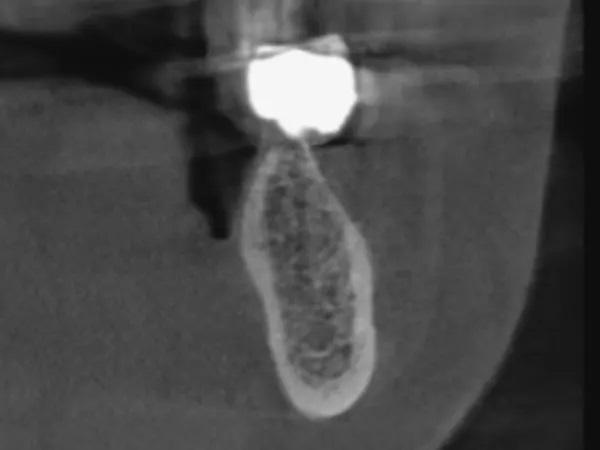

Фото 3: КЛКТ перед операцией, левый первый моляр нижней челюсти.